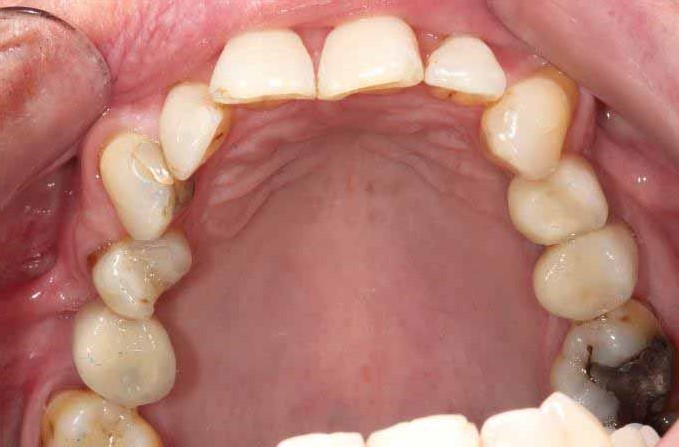

Full mouth Treatment – missing upper front teeth and mispositioned implants in the Lower left side meant planning was key here to get the desired result. Implants were placed to replace the missing teeth, veneers/crowns on the remaining upper teeth allowing an improvement in overall shape and colour, and the implant crowns on the lower left were change to bring into the line of the bite.